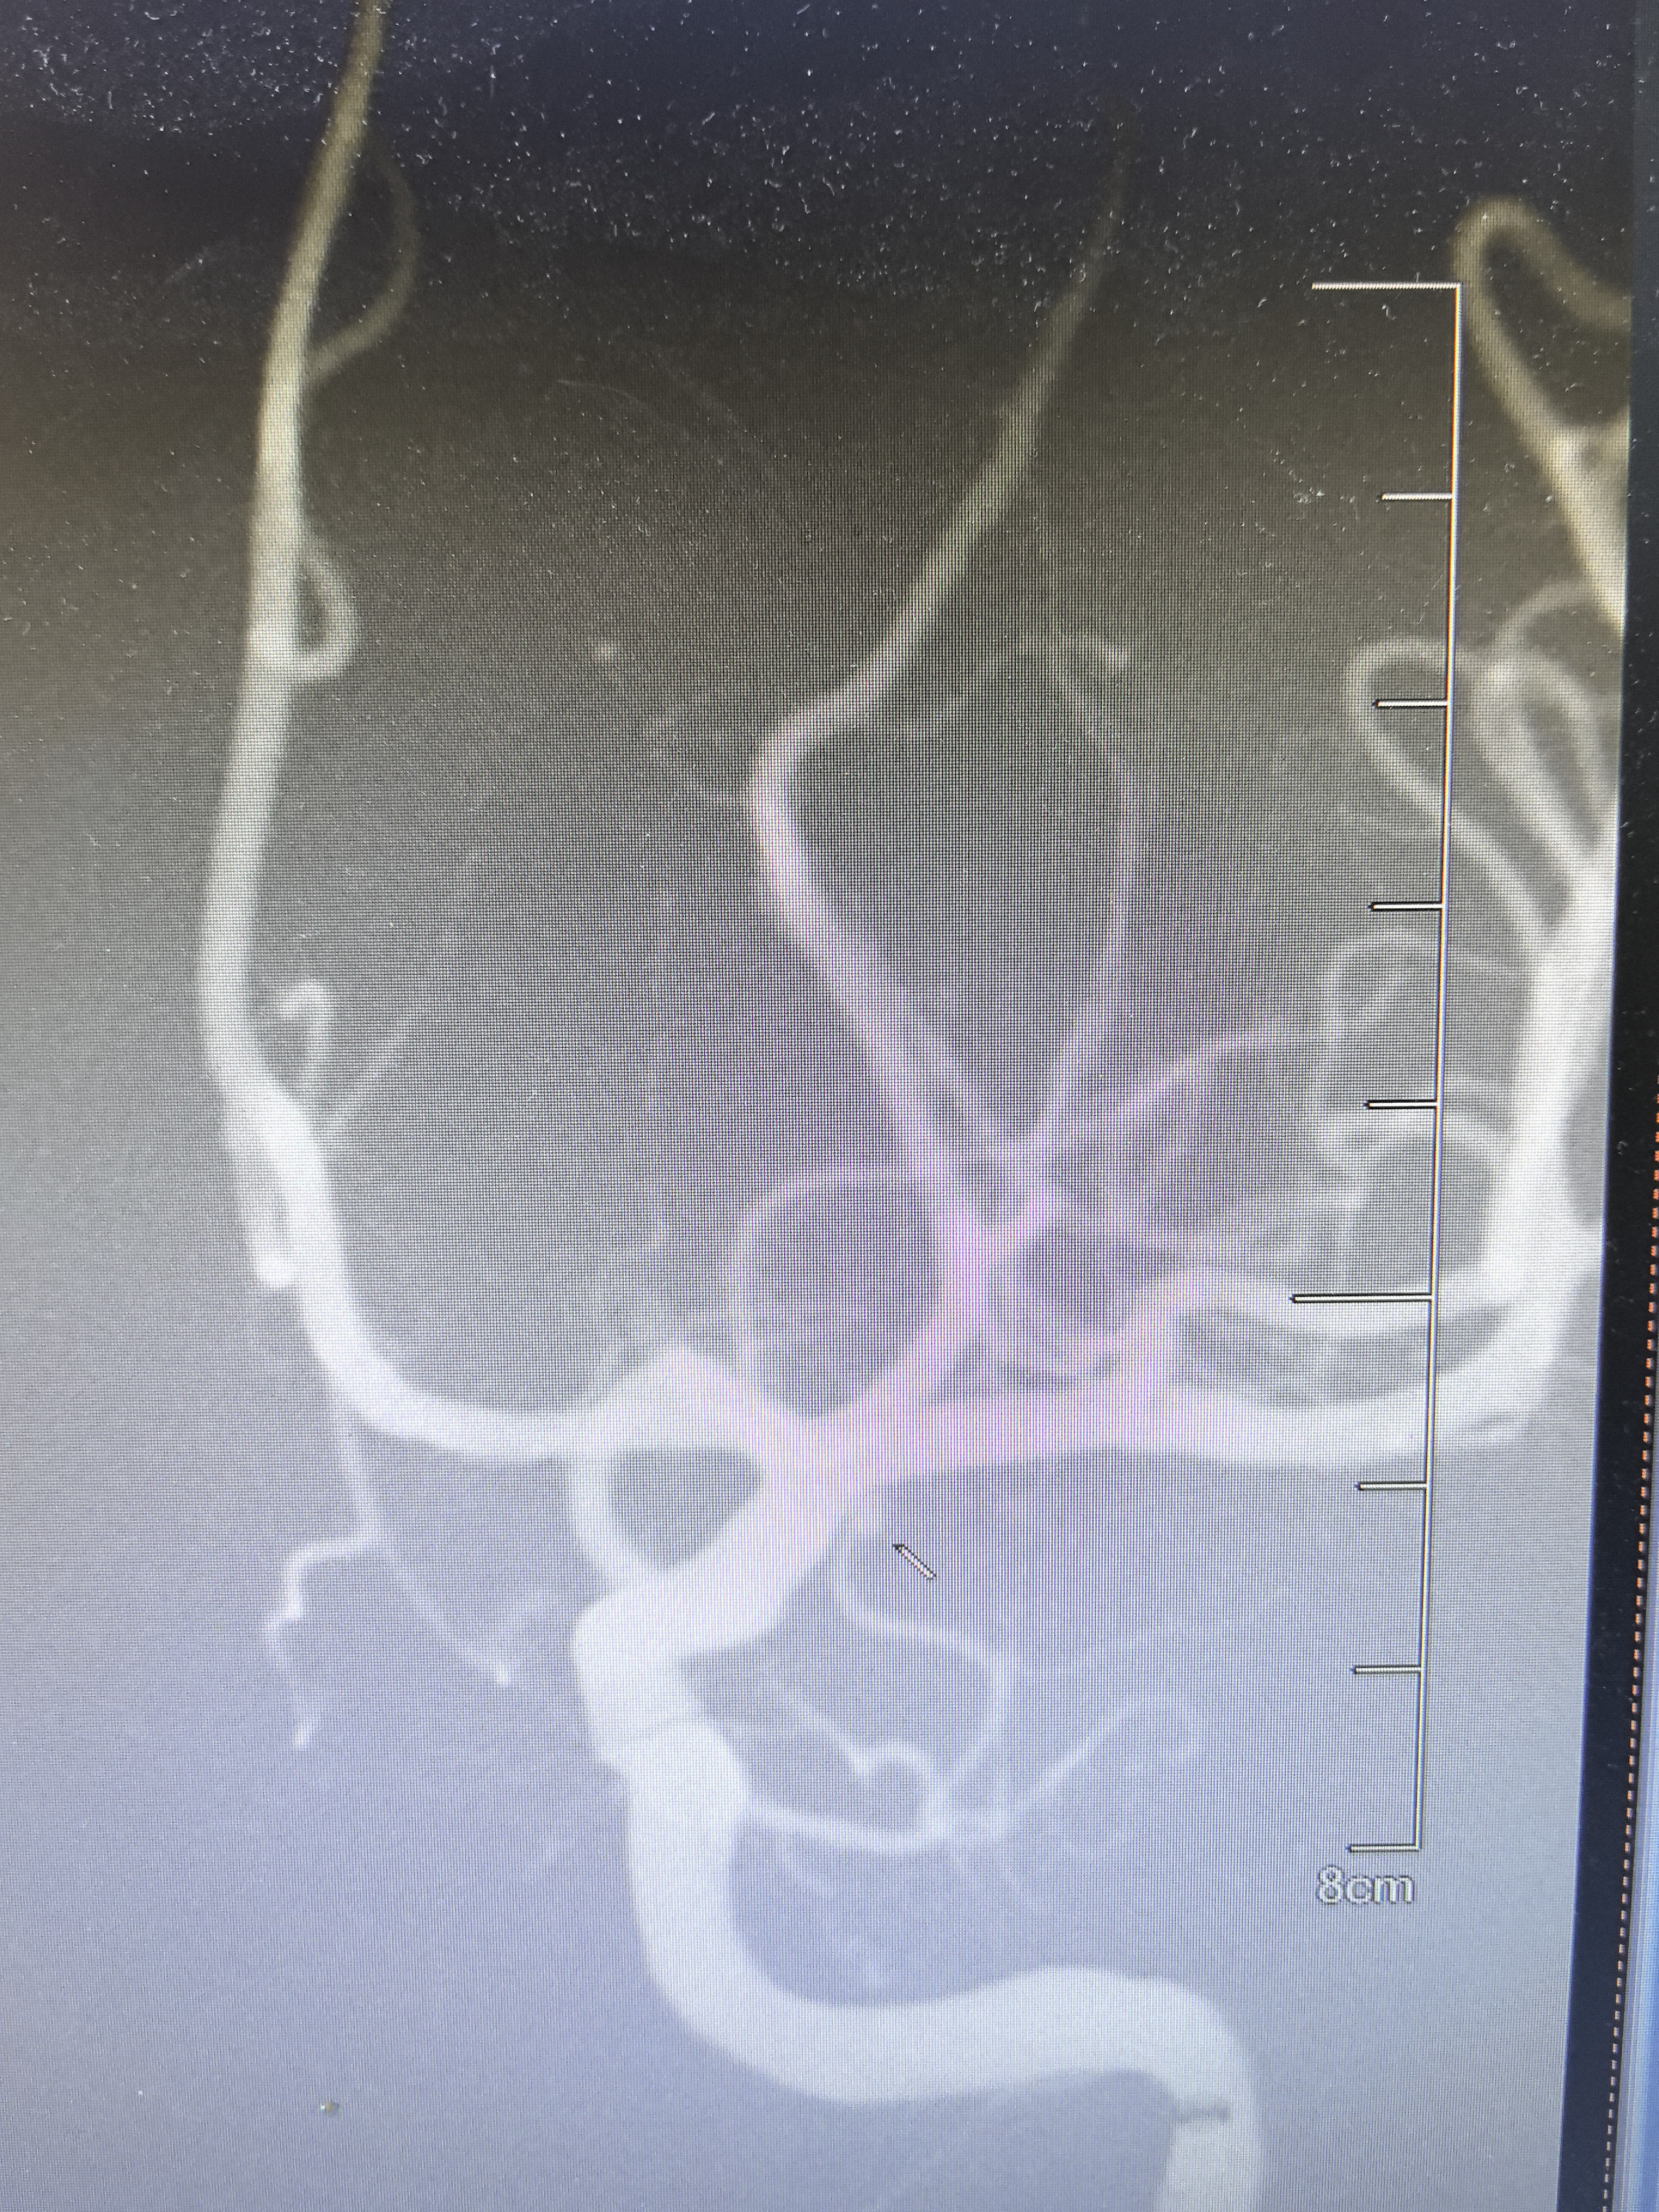

弹簧圈尝试栓塞

解脱弹簧圈后微导管弹出

造影显示动脉瘤栓塞满意,术闭。